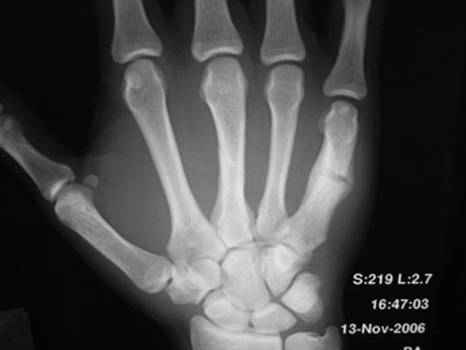

Больной с 4-х дневной травмой кисти

Косой перелом 3 пястной и повторный перелом 5 пястной кости на фоне старой мозоли

- со слов предыдущая травма около месяца назад. Какова тактика лечения ?